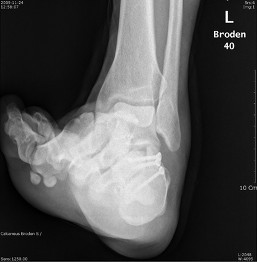

Broden view

촬영목적 : Subtalar joint의 골절시(comminuted fracture) 관절의 관련 여부를 관찰

촬영자세 : Supine 자세로 다리와 카세트 중앙은 일치하도록 하며,internal oblique자세에서 발목관절이 90˚ 굽힌상태를 유지하도록 발을등쪽으로 굽힌다.

중심선 :  cephalic 10˚ ,20˚, 30˚, 40˚ 로  Lateral malleolar에서 아래앞쪽으로 2~3Cm 떨어진지점에 입사한다

촬영Point : Subtalar Joint가 열려져 나타나며,10˚에서는 뒤쪽관절면의 뒷부분,20˚~30˚에서는 Sustentaculum(재거돌기)과 talus(거골)사이의 관절,40˚에서는 앞부분이 잘나타나야한다.